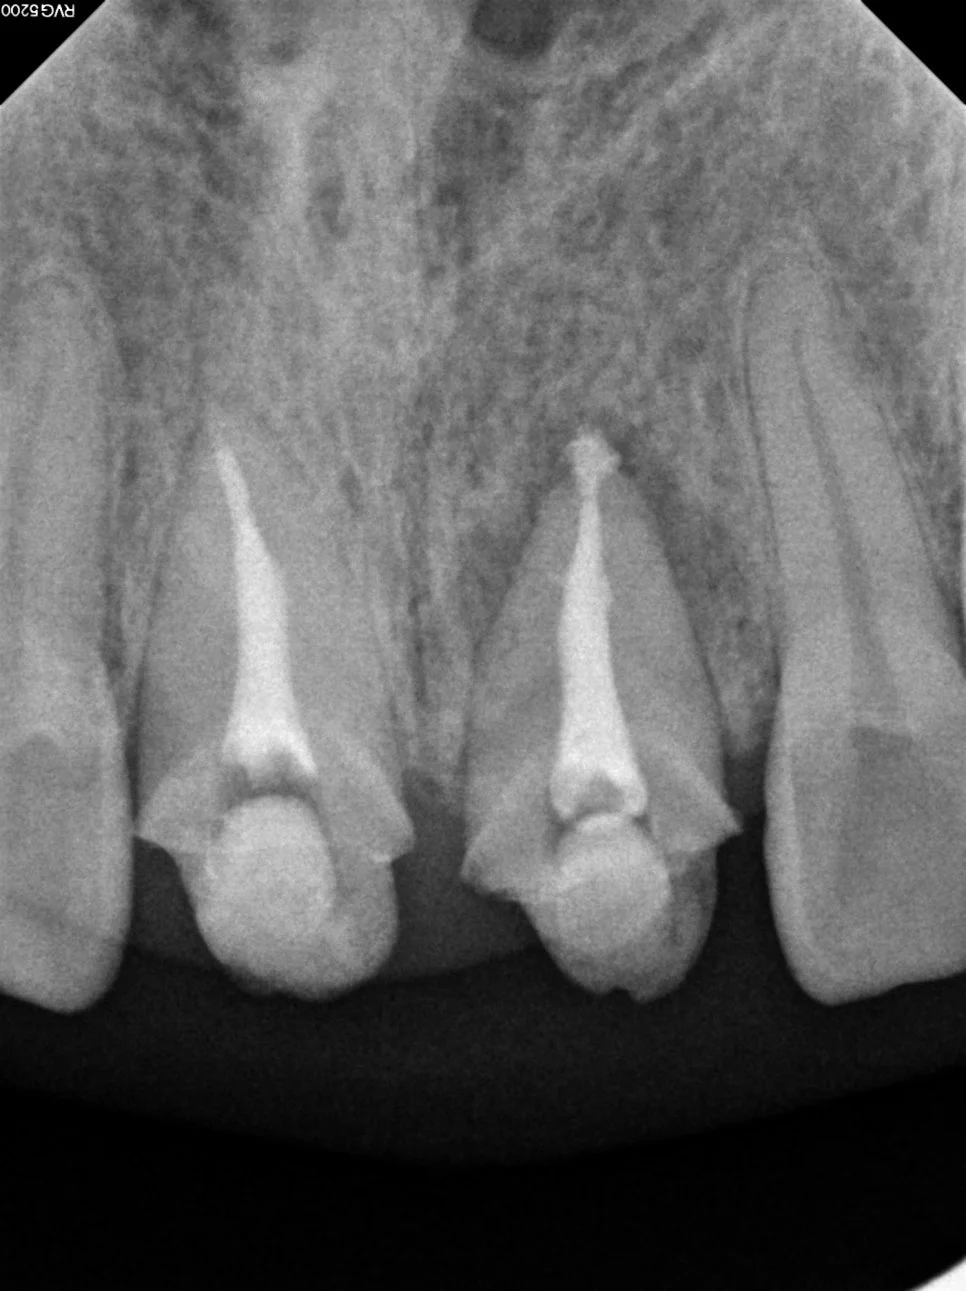

치근단 사진 — 뿌리 끝 염증 소견 관찰

치근단 사진에서 뿌리 끝 염증 소견이 관찰되어 크라운 제거 후 내부 상태 확인과 재신경치료가 필요하다는 결론에 도달했습니다.

재신경치료 — 신경관 확대 및 소독 과정 엑스레이

각 신경관이 뿌리 끝까지 제대로 이어져 있는지 경로를 먼저 확보하고, 안쪽에 남아있는 염증·세균을 없애기 위해 충분히 넓히고 소독해 줍니다.

재신경치료 완료 — 신경관 빈틈없이 충전 확인

마지막으로 신경관 전체를 빈틈 없이 충전해 줍니다.

치료가 끝난 후에는 X-ray를 통해 모든 신경관이 뿌리 끝까지 깔끔하게 차 있는지 확인하면 성공적인 재신경치료가 이루어진 것입니다^^